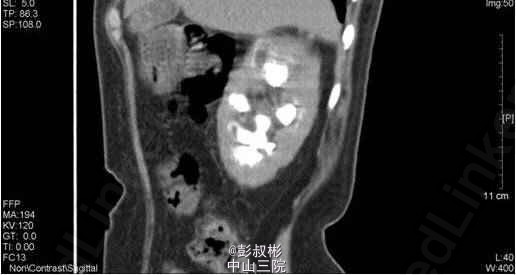

1、因“反复下腰部胀痛伴发热2月,加重10天” 入院。入院前最高体温39.5℃ ,外院检查尿隐血及尿白细胞3+,进一步行泌尿系B超显示双肾及左输尿管下段结石,左肾重度积液 。 2、既往史: 10年前因肾结石行体外冲击波碎石术,自诉术后恢复良好。 3、辅助检查:1) 血常规(抗炎后)、血生化(补钾后)、肝功、凝血、术前八项、胸片及心电图未见明显异常; 2) 尿常规:12.9 :尿液白细胞+++ 尿液红细胞++ 左肾造瘘液白细胞++ 左肾造瘘液红细胞++ 3) 真菌培养:无真菌生长 4) 肾功能:12.9: 肌酐5.68 mmol/L尿素氮: 186 nmol/L 5) 核素肾动态显像+GFR双血浆测定 1.右肾灌注、功能中度受损,右上尿路慢性梗阻。 2.左肾灌注、功能中度受损,左上尿路机械性梗阻。 灌注相:双肾于腹主动脉显影后2秒开始显影,放射性灌注明显减低(右肾明显低于左肾)。灌注曲线分析:双肾灌注峰明显减低。 功能相:右肾影稍增大,放射性摄取明显减低,放射性分布不均匀,可见多发放射性分布稀疏缺损区,放射性排泄缓慢。左肾增大,放射性摄取减低,放射性分布不均匀,可见多发放射性分布稀疏缺损区,放射性排泄缓慢,左肾盏见明显放射性滞留。半小时内膀胱可见放射性积聚。 肾图:右肾a段降低,b、c段融合为低水平延长型肾图。左肾a段降低,b、c段融合为持续上升型肾图。双血浆法肾小球滤过率(GFR)左肾为19.7ml/min,右肾GFR为17.9ml/min。 6) 双肾CTU平扫+增强螺旋扫描 1、左肾多发结石、重度积液、肾功能减退,左输尿管膀胱入口处结石,左侧输尿管炎症; 2、右肾多发结石、轻度积液,右肾功能减退,右肾盂及输尿管炎症。 4、诊断:双肾积脓 右肾铸形结石 左肾多发结石 左输尿管下段结石碎石术后 双肾功能减退 5、入院后处理:予以“舒普深” 3.0 Bid 抗感染,12-5 行“B超引导下经皮左肾穿刺造瘘术”,每日引流出约1500ml脓液。肾功能改善后于12-9行“左侧输尿管镜下钬激光碎石取石术”,术程顺利,术后予以舒普深3.0 Bid抗感染,体温正常。昨日下午行“B超引导下经皮右肾穿刺造瘘术”。